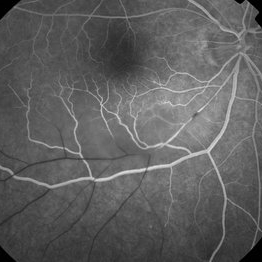

Background: 46-year-old WF with CML (stable on Sprycel) saw her PCP for headaches without known cause; Headaches worsened and became confused, disoriented, off balance, and impaired short term memory. Heme-oncology ordered MRI that showed abnormal signal in the cerebellum and other parts of the brain, and LP has elevated protein. LP did show positive tau test, but fortunately, was a false positive for CJD. IV and PO steroids started and symptoms improved. MRI showed much improvement one month since starting steroids. 3 weeks later had a scotoma in right eye and eye doctor did not find anything at that time to cause it. Tinnitus developed (and some intermittent vertigo before that) and ENT referred back to eye doctor, who then referred the patient to Dr. Zocchi. He found a CWS and BRAO superitemporally OD, and bilateral arteritis (see initial FA). She had some additional work-up for vasculitis. Given the retinal arteritis, cochlear issues, and MRI findings, Dr.Zocchi suspected Susac's Syndrome. She was started on multiple regimens including prednisone, IVIG, azathioprine, and MTX, and has had the best reponse to IVIG. She is stable and doing well with 20/20 vision in both eyes.

Photographer: Maycey Highfill

Imaging device: Topcon

Condition/keywords: Susac's syndrome